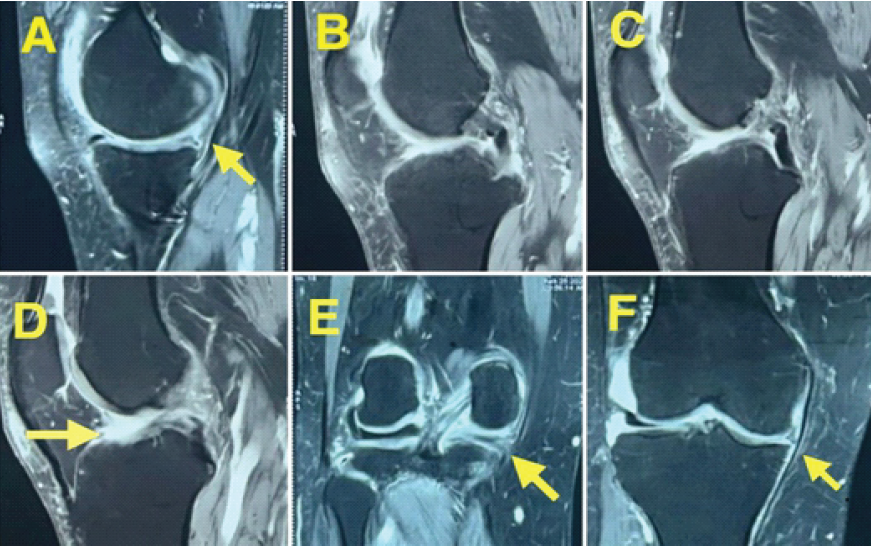

Magnetic resonance imaging (MRI) revealed a complex tear involving the body and posterior horn of the medial meniscus with a near-complete tear of the ACL (Fig. 3).

Figure 3: Magnetic resonance imaging showing complex tear of medial meniscus with an anterior cruciate ligament tear.